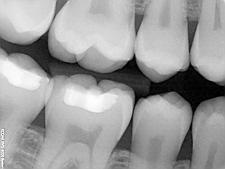

Les radiographies sont très importants pour un diagnostic correct, révélant des conditions qu’on peut pas observer pendant l’examen clinique.